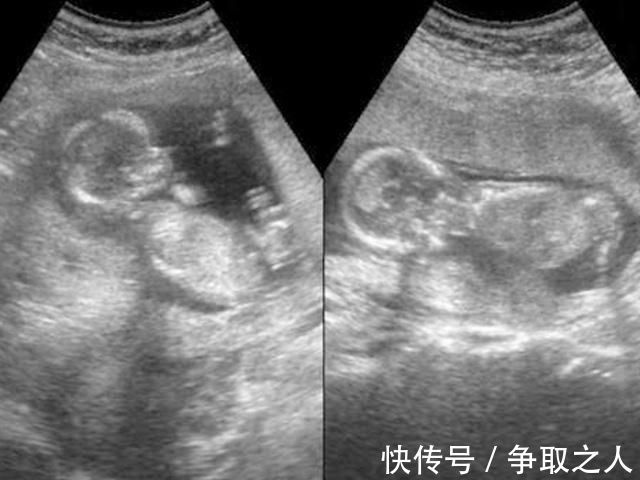

流产|25岁妈妈怀孕7个月引产,看到胎儿的那一刻,她彻底沉默了

25岁准妈妈怀孕7个月引产,之后情绪崩溃

怀孕之后托人查验是儿子,心里就踏实多了,可是到了怀孕7个月的时候,再次查验被告知是女儿,当时她心都凉了。

引产结束,她瞄了一眼,看到已经成型、奄奄一息的胎儿,整个人瞬间崩溃,彻底沉默了。

引产是一个复杂的过程,简单来说就是需要先用一些特殊手段伤害胎儿,再使用一些特殊手段,像正常分娩那样,把胎儿分娩出来,只是分娩得到的是一个健康的宝宝,而引产的结果是一个奄奄一息或者是已经死亡的胎儿。